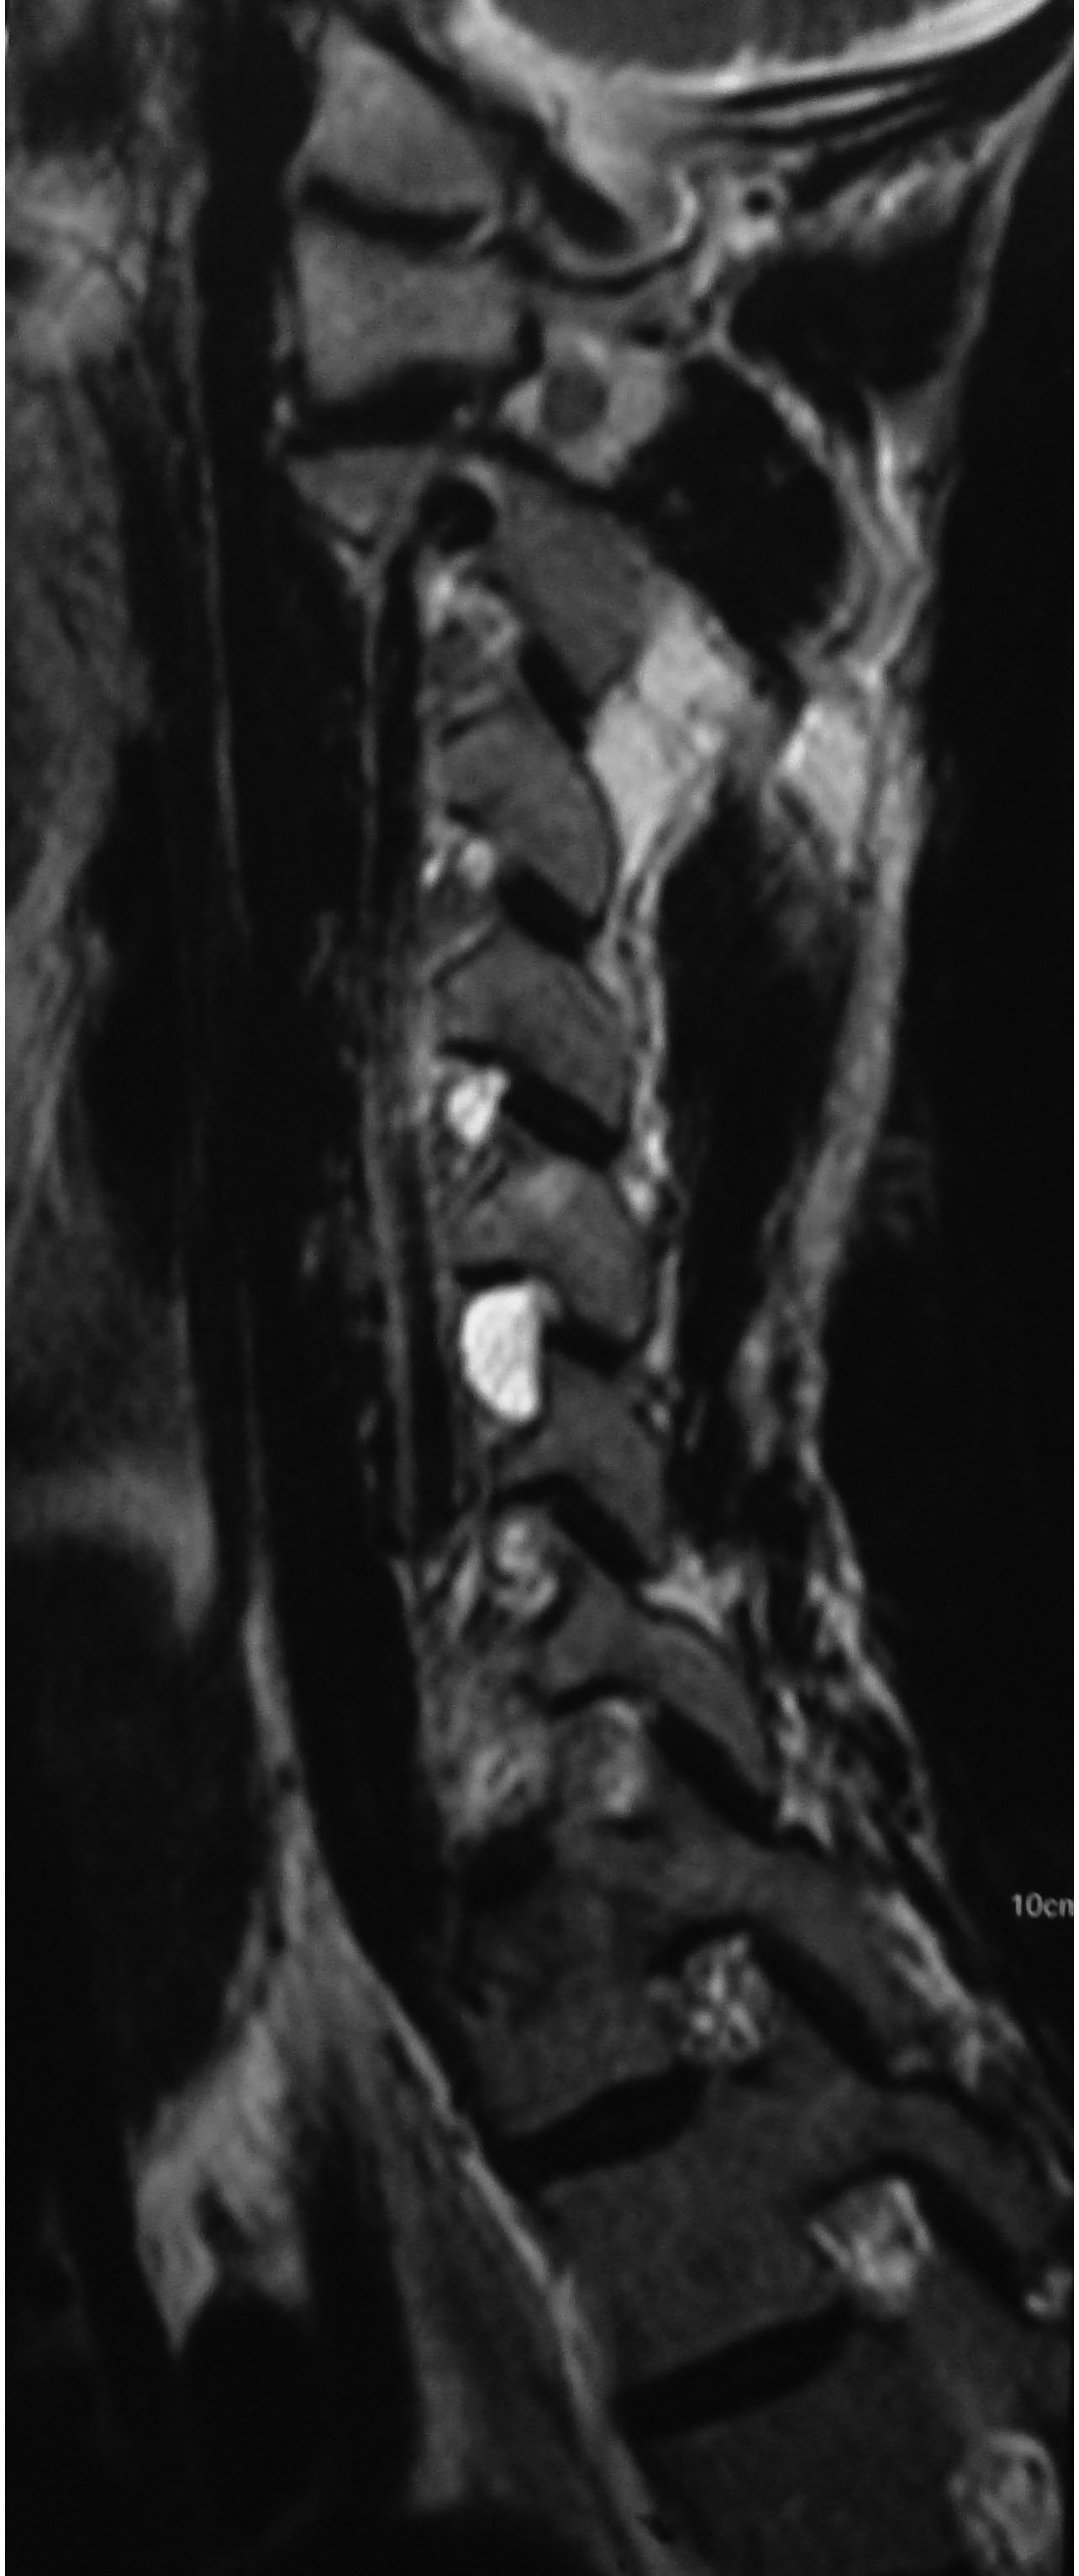

Plain radiographs showed no abnormalities. MRI of the cervical spine was done. Sagittal T2W images showed hyperintense lesion at both C5-C6 neural foramen (Figure 1 & 2). Axial T2W images showed bilateral cervical perineural cyst at C5-C6 neural foraminae (Figure 3A & 3B). Post-contrast study showed no abnormal enhancement along the cysts. EMG-NC studies showed evidence of C5C6 chronic motor axon degeneration at root level. Left deltoid and biceps showed high amplitude large duration motor unit potentials during voluntary activity.

Figure 1 Sagittal T2W image of the cervical spine showing hyperintense lesion at C5-C6 neural foramen corresponding to the right perineural cyst.

Figure 2 Another sagittal T2W image of the cervical spine showing similar hyperintense lesion at C5-C6 neural foramen corresponding to the left perineural cyst.